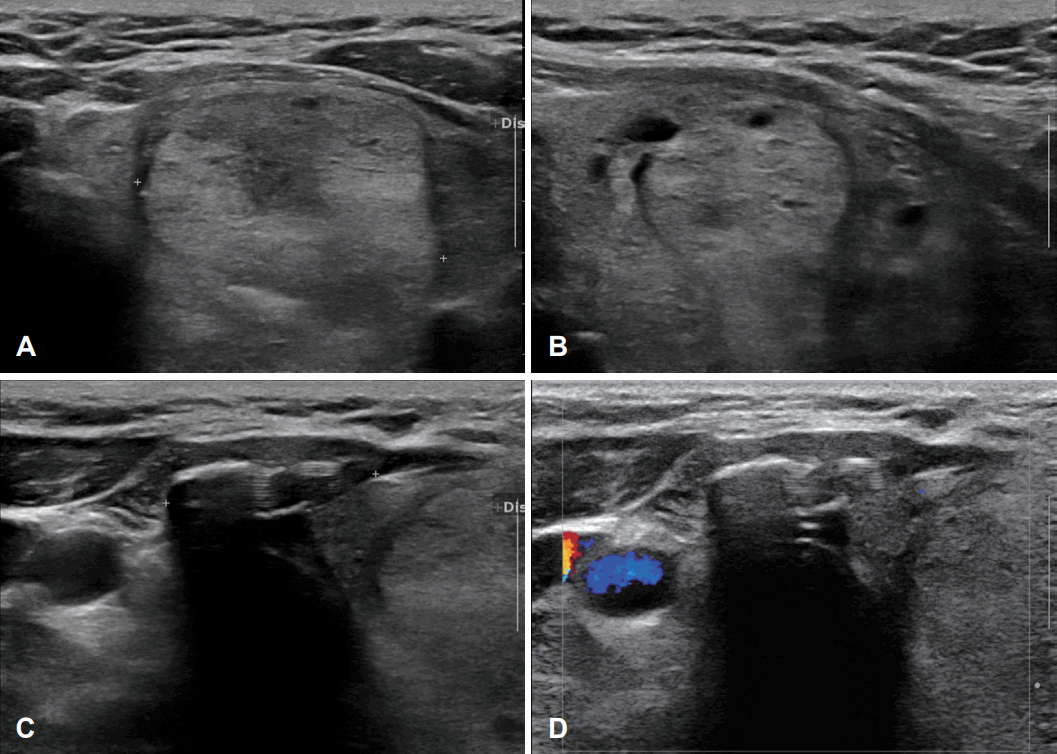

62세 여자 환자가 1년 전부터 좌측의 재발하는 압통과 크기 증가를 동반한 전경부 종물을 주소로 본원 내분비내과로 내원하였다. 1987년 우측 갑상선 일엽절제술 과거력이 있었으며, 갑상선기능검사상 thyroid stimulating hormone (TSH) 0.10 μIU/mL (0.27-5.0), Free T4 1.43 ng/dL (0.93-1.7), thyroglobulin-Ab <10 IU/mL (0-115), antimicrosomal-Ab 18.49 IU/mL (0-34)로 TSH 억제 소견이 확인되었다. 갑상선 초음파 검사에서 좌측 갑상선의 중간부에 30.8×28.7 mm의 크기로 경계가 분명한 혼합 에코성 결절이 보였으며 결절 내부로 미세석회화와 부분적인 저에코 병변을 포함한 결절이 관찰되었다(Fig. 1A and B). 결절의 우측으로 level VI 부위 20.7 mm 크기의 음향음영 및 다중반사를 동반한 혼합성 음영의 병변이 관찰되었다(Fig. 1C and D). 타병원에서 시행한 흉부 전산화단층촬영 검사상 불균질하게 조영 증강되는 좌측 갑상선 결절과 함께 결절의 우측으로 고음영 병변이 관찰되었다(Fig. 2). 경부 전산화단층촬영 검사와 세침흡인검사를 계획하였으나 환자의 거부로 시행하지 못하였고, 수술적 치료 원하여 이비인후과로 의뢰되었다.

Preoperative ultrasound images. A and B: 30.8×28.7 mm sized well-defined heterogenous echoic nodule with microcalcification in left thyroid lobe. C and D: 20.7 mm sized ill-defined hypoechoic lesion with posterior acoustic shadowing in right level VI.